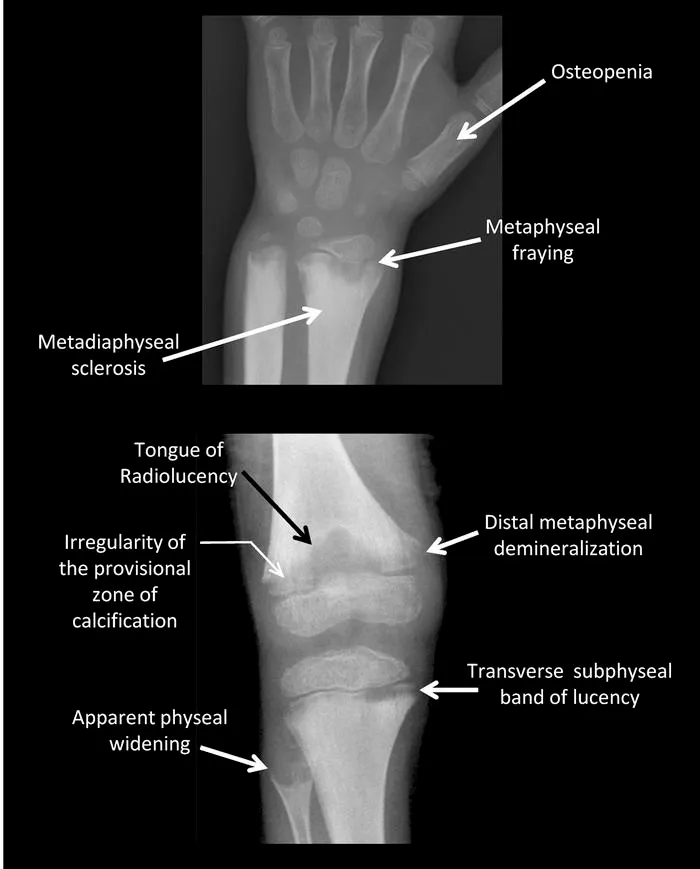

- X-Ray Findings (Metaphysis): Cupping, fraying, splaying.

⭐ First radiological sign of healing is the appearance of the line of provisional calcification (usually within 2-4 weeks).

- Rickets (Vitamin D deficiency) shows cupping, fraying, and splaying of metaphysis on X-ray, with rachitic rosary clinically.